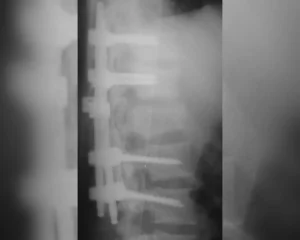

- Cirurgia de Urgência (Descompressão e Fixação): Quando há compressão da medula por fragmentos de osso ou disco, a cirurgia deve ser feita o quanto antes para “liberar” o tecido nervoso. Além disso, utilizamos parafusos e hastes para estabilizar a coluna e permitir que o paciente possa ser mobilizado com segurança pela equipe de fisioterapia.